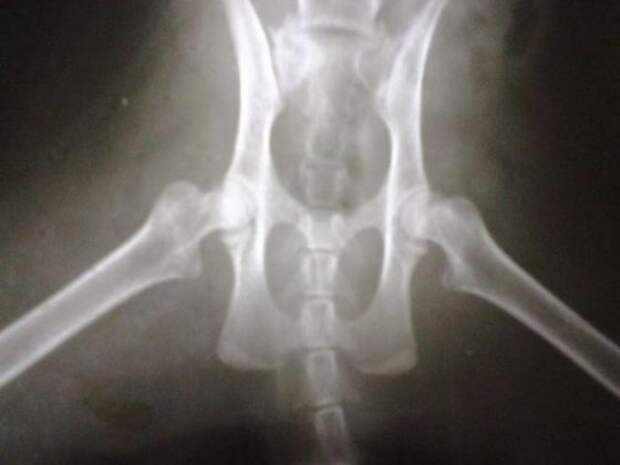

Кот был грязным, с пролежнями и колтунами, глаза гноились, а задние лапы были парализованы.

Прежде чем показаться ветеринару, котика решили отмыть и выстричь колтуны. Задние лапы обездвижены и вывернуты в обратную сторону.